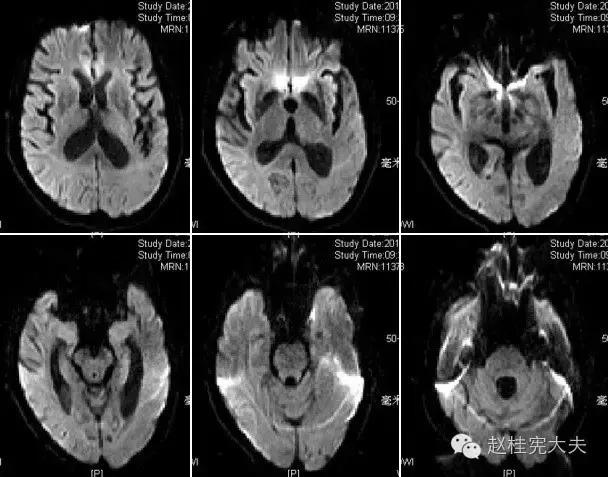

上周,于发病后2月复查磁共振:

到此为止,MELAS的诊断应该在没有基因确诊的情况下在临床上得到认可了,患者明确诊断为线粒体脑肌病伴乳酸血症和卒中样发作(MELAS),解释了患者的所有症状,患者母亲不明原因地死亡也得以真相大白,患者的相关亲属们在未来的人生路上也多了一份呵护......